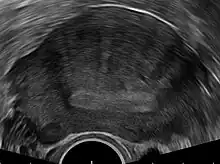

Transvaginal ultrasonography

Transvaginal ultrasonography is a cheap and readily available imaging test that is typically used early during the evaluation of gynecologic symptoms.[24] Ultrasound imaging, like MRI, does not use radiation and is safe for examination of the pelvis and female reproductive organs.[25] Overall, it is estimated that transvaginal ultrasonography has a sensitivity of 79% and specificity of 85% for the detection of adenomyosis.[11]

Common transvaginal ultrasound findings are defined by the European MUSA group in 2015 [26] and are defined in 2022 by the MUSA group.[27] The ultrasound characteristics can be divided in direct and indirect features.

Direct features:

- myometrial cysts - pockets of fluid within the smooth muscle of the uterus

- Hyperechogenic islands - usually white endometrium islands within the myometrium

- Echogenenic subendometrial lines and buds - usually white lines and knobs attached to the endometrium, prtruding into the myometrium.

Indirect features:

- Globular, enlarged, and/or asymmetric uterus

- Fan shaped shadowing - differentiating from fibroids with linear shadowing

- Anterior/posterior wall asymmetry

- Translational vascularity - diffuse spread of small vessels within the myometrium

- Irregular or interrupted junctional zone - the borderline between the endometrium and myometrium

The power Doppler or Doppler ultrasonography function can be used during transvaginal ultrasonography to help differentiate adenomyomas from uterine fibroids.[24][28][29] This is because uterine fibroids typically have blood vessels circling the fibroid's capsule. In contrast, adenomyomas are characterized by widespread blood vessels within the lesion.[24] Doppler ultrasonography also serves to differentiate the static fluid within myometrial cysts from flowing blood within vessels.[24]

The junction zone (JZ), or a small distinct hormone-dependent region at the endometrial-myometrial interface, may be assessed by three-dimensional transvaginal ultrasound (3D TVUS) and MRI. Features of adenomyosis are disruption, thickening, enlargement or invasion of the junctional zone.[21] There is no consensus about the actual histology of the junctional zone and a recent review showed that the ultrasound, MRI and histology all define and describe the junctional zone differently.[30]